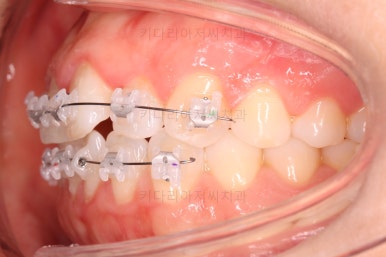

부산나비앞니교정 키다리아저씨치과에서 치료를 한 지 3개월째의 모습입니다.

굉장히 많이 가지런해 진 것을 볼 수 있어요.

그래도 여전히 나비앞니의 느낌이 남아있어서 미세한 조절을 더 하고 마무리를 하기로 했습니다.